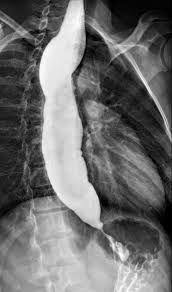

Three tests are commonly used to diagnose achalasia: Barium swallow: For this test, you’ll swallow a barium preparation (liquid or other form) and its movement through your esophagus is evaluated using X-rays. The barium swallow will show a narrowing of the esophagus at the LES. Upper endoscopy: In this test, a flexible, narrow tube with a camera on it – called an endoscope – is passed down your esophagus. The camera projects images of the inside of your esophagus onto a screen for evaluation. This test helps rule out cancerous (malignant) lesions as well as assess for achalasia. Manometry: This test measures the timing and strength of your esophageal muscle contractions and relaxation of the lower esophageal sphincter (LES). Failure of the LES to relax in response to swallowing and lack of muscle contractions along the walls of the esophagus is a positive test for achalasia. This is the “gold standard” test for diagnosing achalasia.